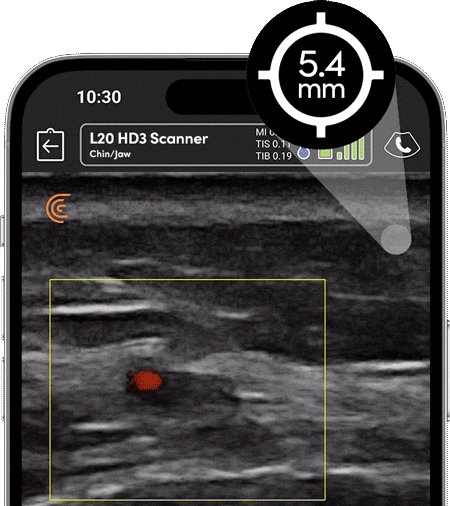

Using ultrasound to guide filler placement reduces the risk of complications and helps to monitor the filler over time, allowing you to decide when to dissolve or refresh the filler. Color and power Doppler are essential tools for managing vascular complications.